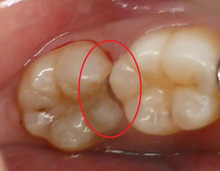

レントゲンを撮影しました。

素人目にはわからないかもしれませんが・・・

赤い丸印内に 黒い影が見えます。

これが もし虫歯です。

レントゲンを撮らなければ 絶対に 見逃します。

隠れ虫歯がありました。